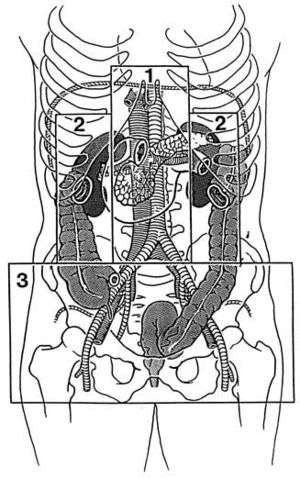

Classification of traumatic retroperitoneal hemorrhage[3]

- Zone 1: Central

- Pancreaticoduodenal injuries, major vascular injury

- Zone 2: Flank/Perinephric

- Renal trauma, ureteric or colonic injury

- Zone 3: Pelvic

- Pelvic fracture or ileofemoral vascular injury